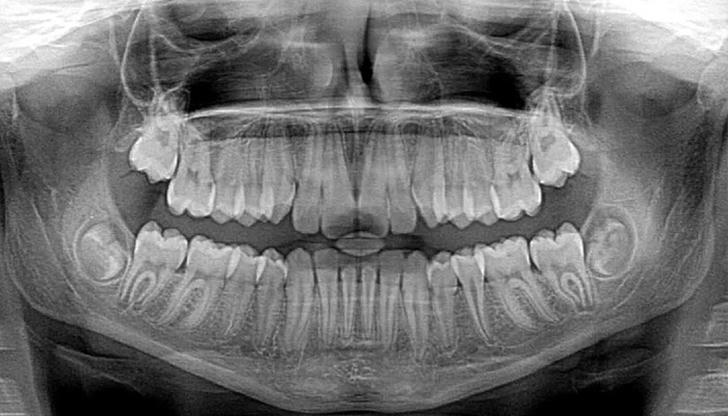

What is the purpose of dental X-rays?

Correct Incorrect X-rays reveal problems not visible to the naked eye, such as cavities between teeth or issues below the gum line.